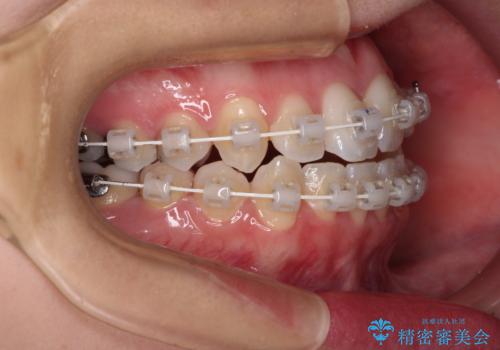

- 上下前歯のデコボコを気にして来院された患者様です。

上顎骨の横幅が狭く、奥歯は上顎よりも下顎が外側にある咬合状態でした。

歯列矯正では基本的に骨格を改善することはできませんが、急速拡大装置(MARPE)を使用することで上顎骨を側方に拡大させることができ、咬合状態を大きく改善することができます。

事前に急速拡大装置で側方拡大を行い、上下を目立たないワイヤー装置により歯列を整えていくこととしました。